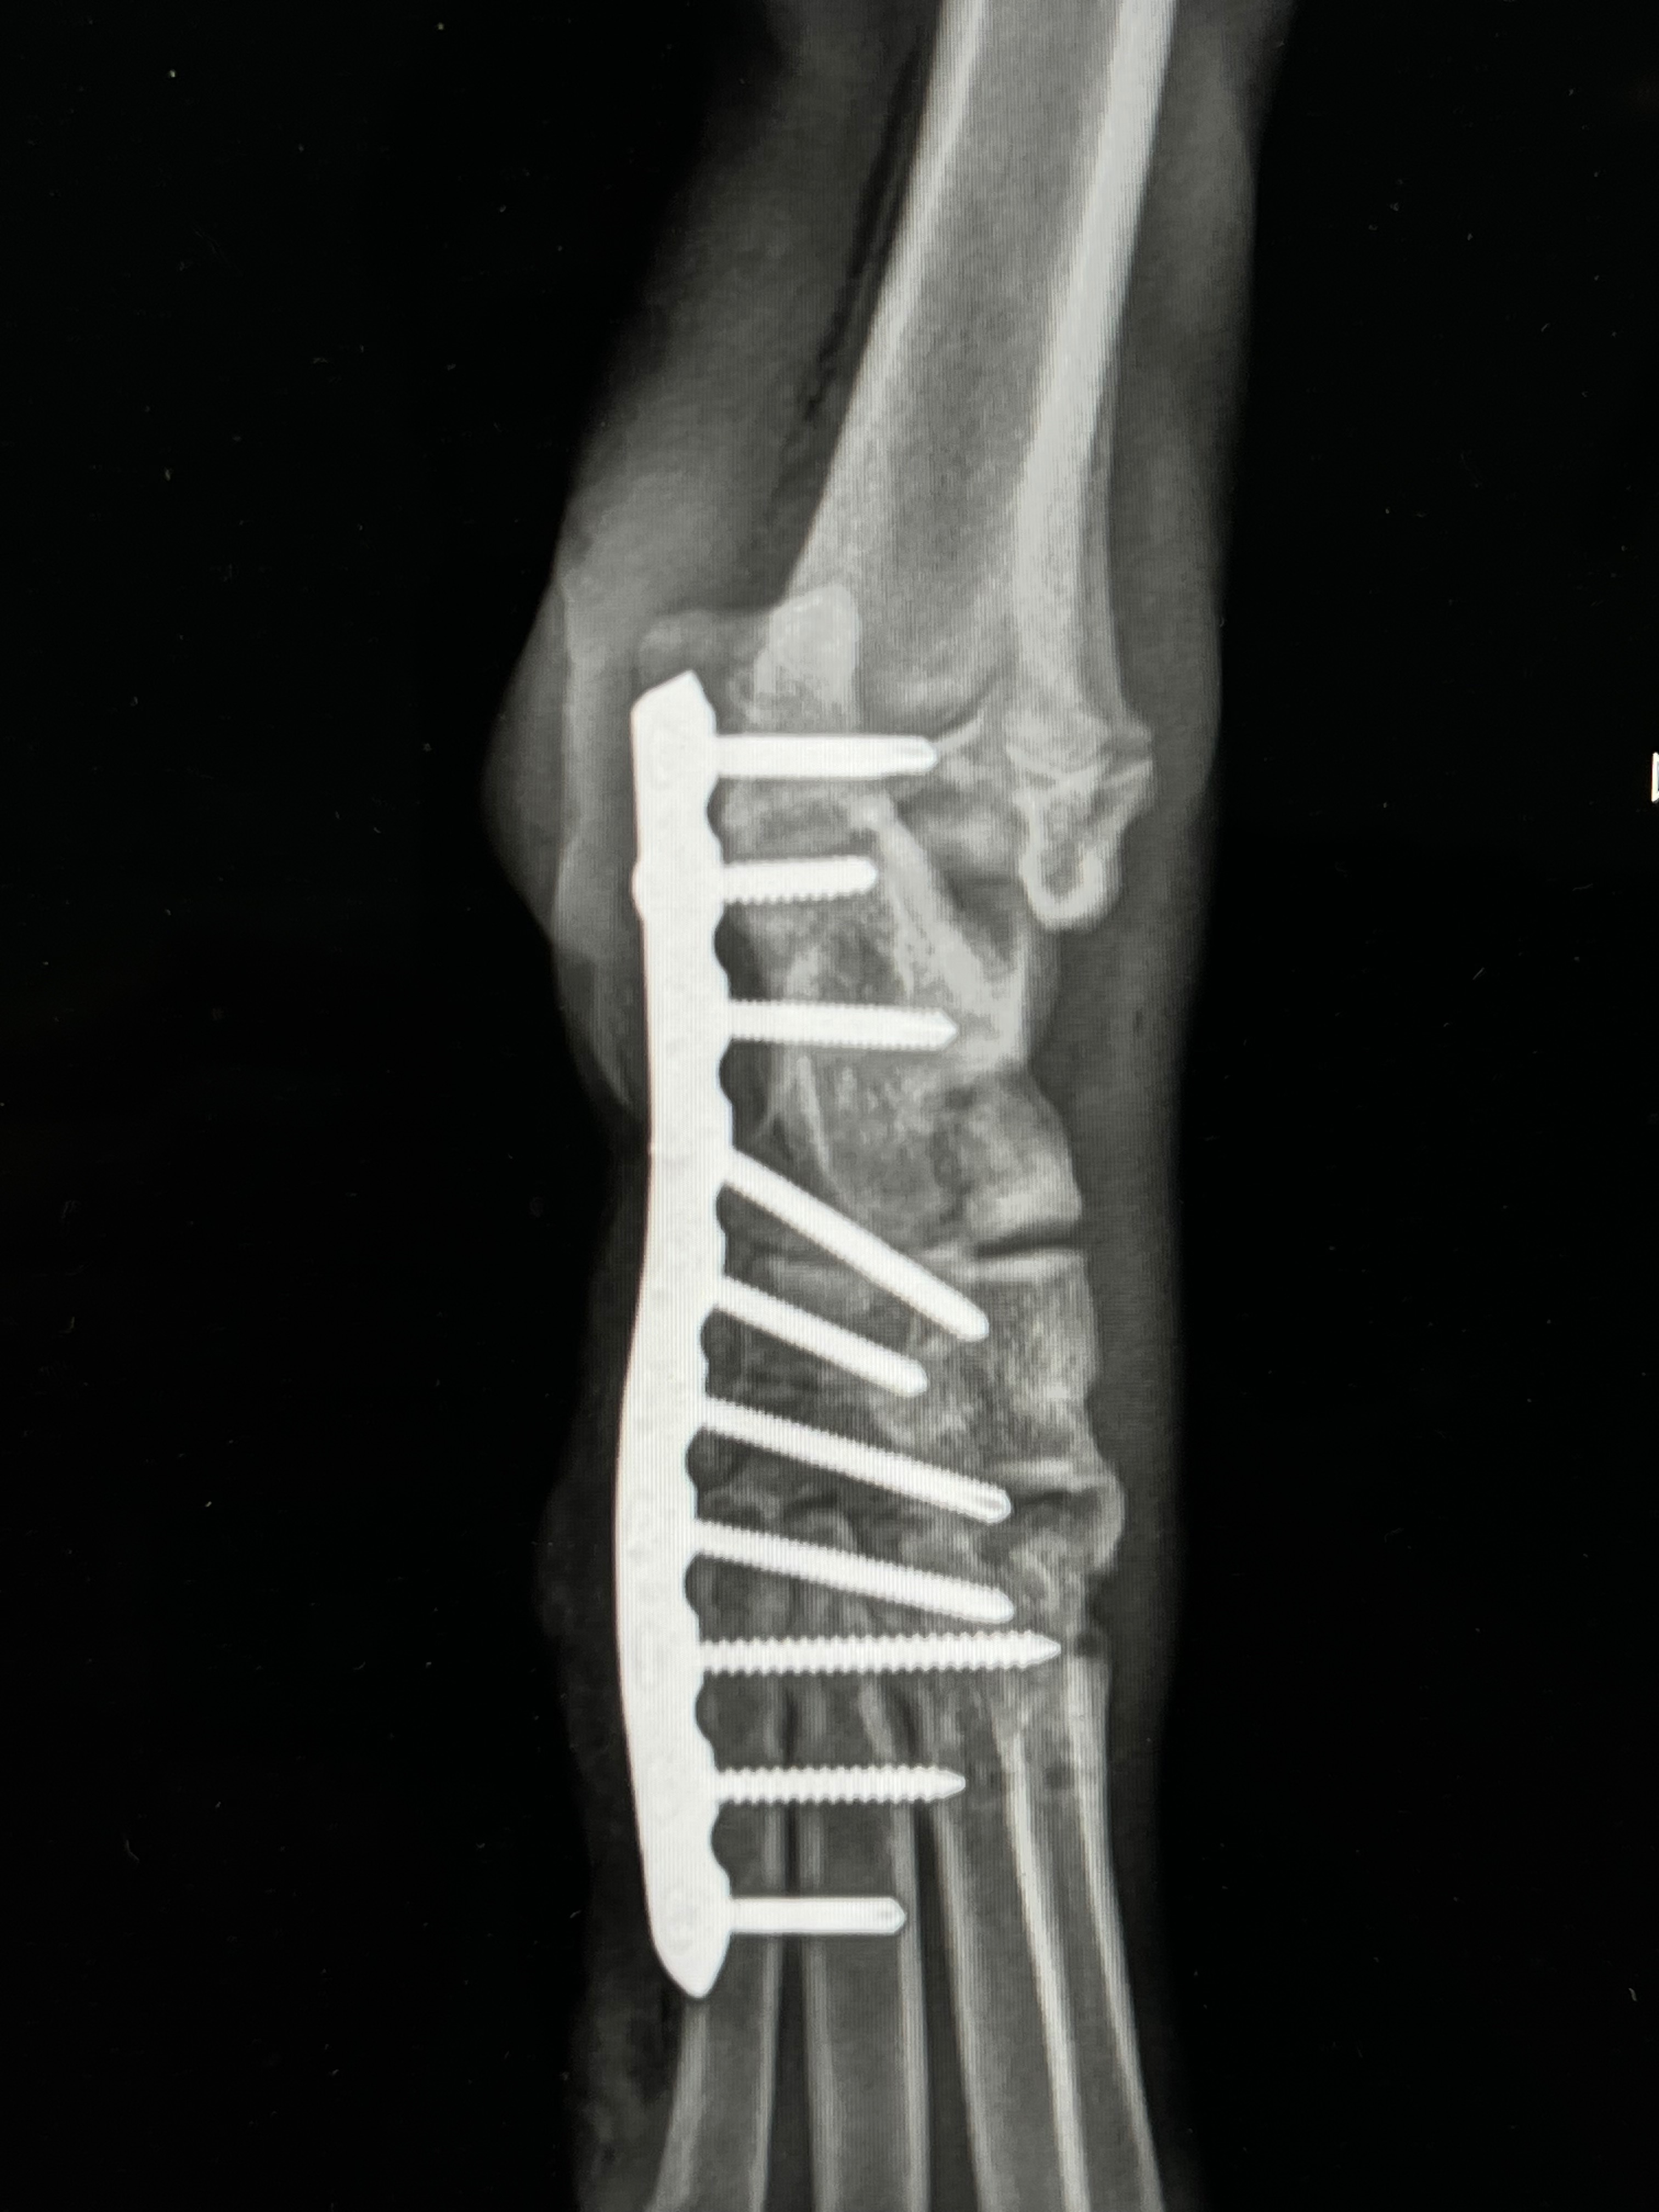

I took full responsibility for her and rushed her to the ER. X-rays confirmed the worst:

Her back leg was broken in 5 places, and one bone was completely separated from the joint. Surgery was her only hope to keep the leg—and survive.

Because of YOU, Gemma received the emergency surgery she needed. A metal plate was inserted to stabilize her growing bones and begin the long road to recovery.

• She will need a second surgery down the line to remove the metal plate